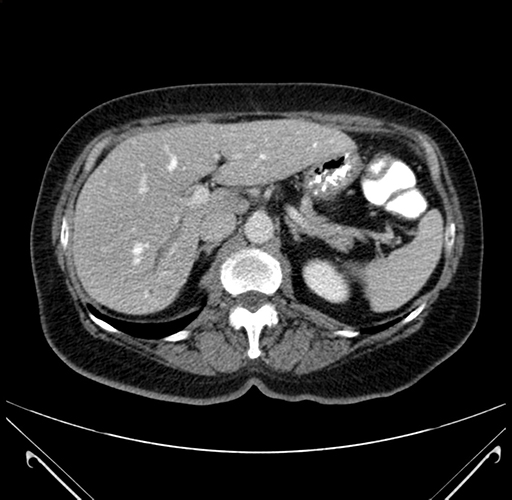

Pre-Chemo: Axial Venous

Axial Venous